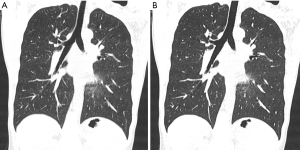

Iterative reconstruction: how to overcome the changes in image texture

In spite of the considerable advantages of quantitation, only a few quantitative imaging scores are used in clinical decision-making due to several obstacles: (I) Difficulties in the harmonization of data acquisition and analysis, (II) lack of international standards without routine quality assurance (QA) and quality control (QC) processes, (III) poor validation of quantitative biomarkers that are subject to errors in interpretation (69). For example, several trials indicate that automated quantification of emphysematous lung changes is highly reproducible, when identical scan parameters and reconstruction algorithms are used (5). Yet, different scanners and especially different reconstruction algorithms might hamper the reliable function of semiquantitative and quantitative approaches due to the different image appearance (Figure 7): different authors have already criticized iterative reconstruction (IR) techniques in visual approaches for the artificial texture of the reconstructed images and the appearance changes of images reconstructed with IR (73,74). Martini et al. (75), for example, found that the use of IR techniques was not beneficial for increasing sensitivity for the detection interstitial lung changes in reduced dose protocols, despite image noise was reduced.

Messerli et al. (76), who evaluated the impact of IR and reduced dose CT on quantitative emphysema evaluation, found that the mean lung attenuation of reduced dose CT was significantly altered by IR. In addition, the agreement of mean lung attenuation between standard dose and reduced dose CT with IR was poor; and the agreement between standard and reduced dose CT without the use of IR was substantial. These findings imply that for CT with reduced dose protocols or IR an adaptation of the generally accepted and recommended thresholds for HU values (24,25) is necessary in order to distinguish emphysematous lung parenchyma from normal lung tissue. Since the agreement between standard and reduced dose CT without the use of IR was substantial, a different approach could be applied: for mere quantification, images not post-processed with IR algorithms could be used, while using the post processed only for the visual assessment.